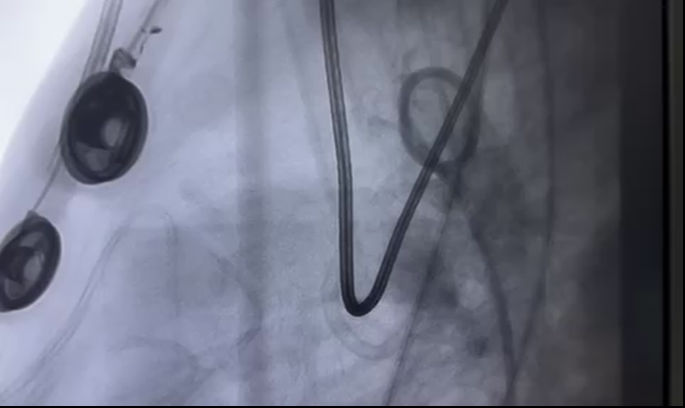

7月5日上午,在家人饱含期待又夹杂着担忧的目光中,亮亮被送入了手术室。全身麻醉、气管插管、血管穿刺、缺损定位、封堵器释放……在麻醉手术中心、超声诊断科等多学科紧密配合下,陈玺全副主任团队为亮亮实施了经皮动脉导管未闭封堵术。每一步都是行云流水,一气呵成,在场的医护人员都小心翼翼地,用自己的方式呵护着一颗颗小心脏。

亮亮术中封堵器顺利置入